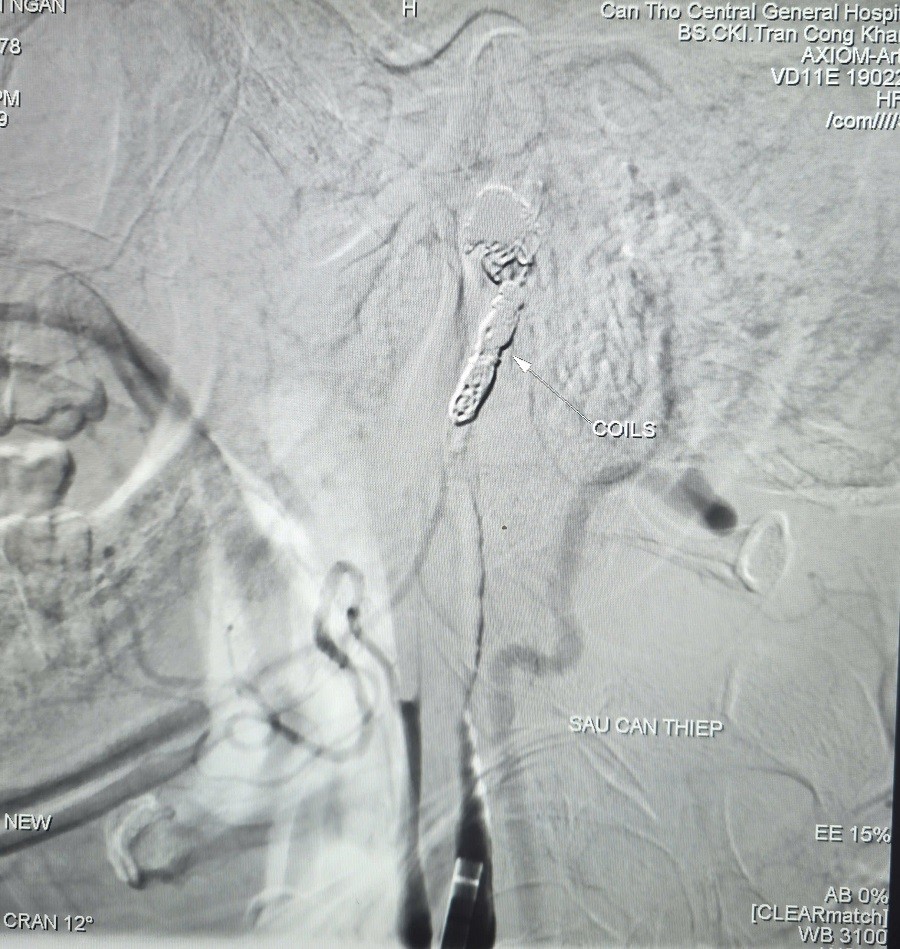

Không còn hình ảnh thoát mạch sau can thiệp

Các bác sĩ đã dùng bóng chẹn dòng chảy kiểm soát lượng máu chảy ra từ túi phình và tiếp tục luồn vi ống thông (ống thông siêu nhỏ) chọn lọc đến vị trí túi phình và tiến hành thả 09 vòng xoắn kim loại (coils) để gây tắc hoàn toàn ổ giả phình và động mạch cảnh trong phải, nhằm kiểm soát triệt để nguồn chảy máu.

Chụp kiểm tra từ động mạch cảnh trong trái cho thấy có tuần hoàn bàng hệ nuôi bán cầu não phải qua động mạch thông trước, đảm bảo tưới máu não sau can thiệp. Thời gian hoàn tất can thiệp là 90 phút.